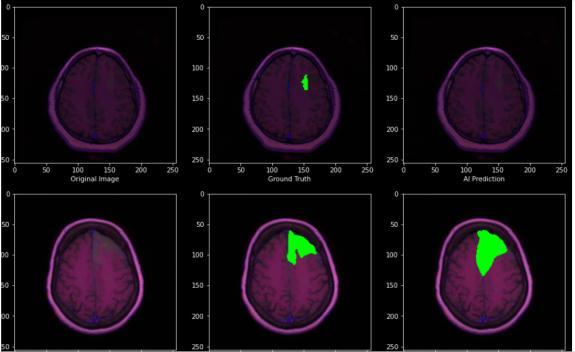

Fig.4.4.3.PredictedOutput

We use three separate segmentation tasks to show the u net in action. The segmentation of neural structures in recordings made using an electron microscope is the first challenge. We employed a brain tumor segment dataset for this experiment, which is accessible online. 3064 MRI scans and 3064 masks are included. A collection of 30 images serially sized 512x512 section which transmits throughelectronmicroscopyoftheventralnervecordofa Drosophila serves as the training data (VNC). To proceed with the implementation and classification, the ground truth data which is completely tagged for each image is consideredforthewhiteandbackmatteroftheimages.U netmodelhasbeenchosenfortheexperimentationasthis model does not need any further processing either before or after diagnosis which internally makes the model less pronefortheerrorsandaswellensurethatitoutperforms otherclassifierswhichmayneedtobetrainedwithstrong featuremapsaftercarefulprocessingofthedata.However theU netmodelalsosuffersawarpandrandomerror.

© 2022, IRJET | Impact Factor value: 7.529 | ISO 9001:2008 Certified Journal | Page2343 The following Neural Network architectures have been experimented for classification of multigrade and their performancehasbeenrecorded: 4.4.U Net: Fig.4.4.1.Accuracygraph

Fig.4.4.2.PredictedGraph